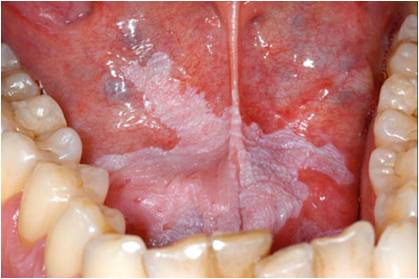

口腔白斑病

口腔白斑病一侧口腔黏膜网状白斑图.jpg

口腔白斑